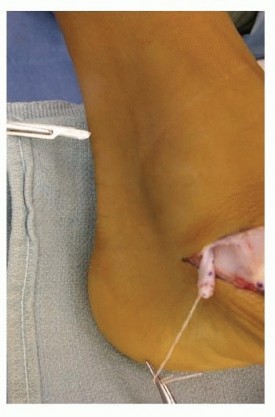

Achilles Tendon or Gastrocnemius LengtheningAssess the equinus contracture by the Silfverskiöld test with the subtalar joint inverted to neutral and the knee both flexed and extended.Perform a gastrocnemius recession if 10 degrees of dorsiflexion can be achieved with the knee flexed but not with it extended.Perform an open or percutaneous Achilles tendon lengthening if 10 degrees of dorsiflexion cannot be obtained even with the knee flexed ( TECH FIG 3).

---

TECH FIG 3 • The Achilles tendon or the gastrocnemius tendon is lengthened based on the results of the Silfverskiöld test. (From Mosca VS. Calcaneal lengthening osteotomy for valgus deformity of the hindfoot. In: Tolo V, Skaggs D, eds. Master Techniques in Orthopaedic Surgery: Pediatric Orthopaedics.Philadelphia: Lippincott Williams & Wilkins, 2008 :263-276.)